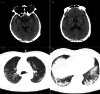

Concomitant neurological symptoms observed in a patient diagnosed with coronavirus disease 2019